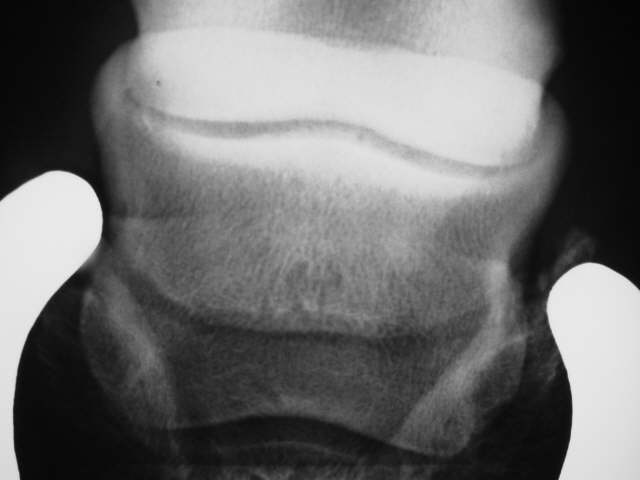

Oseolytische Defekte

Auflösungserscheinungen am unteren Rand und im Zentrum des Strahlbeines. Röntgenklasse IV